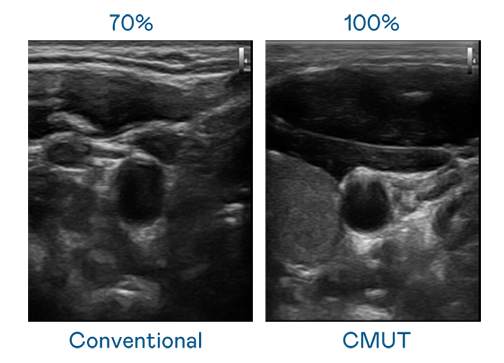

CMUT 技术是一种用电容式微机电元件来产生超音波讯号的技术。与传统 PZT 压电式技术相比,CMUT 频宽增加 30%,更宽频的超音波讯号让影像解析度大幅提升,是实现高影像品质医疗超音波扫描、促进精准医疗发展的关键技术。

大频宽带来超清晰影像

超音波影像的解析度高低,首先取决于探头能发出的讯号频宽。东升国际 CMUT 可提供高清晰的超音波讯号,提供高频宽、高灵敏度、影像纹理细节更高的超音波影像,协助医护人员缩短影像判读时间及利用精准的医疗影像进行诊断。